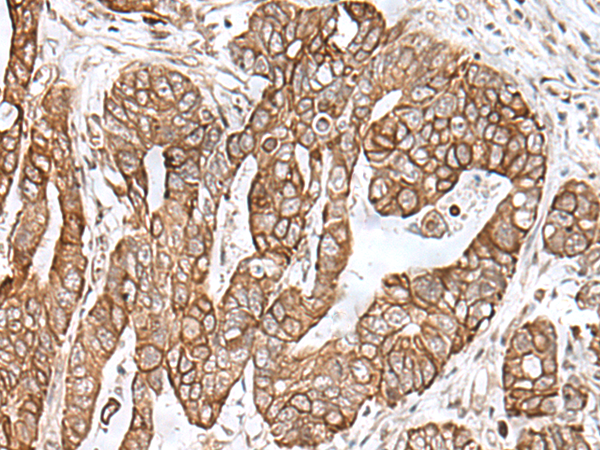

IHC positive control:

Human gastric cancer

IHC Recommend dilution:

50-300